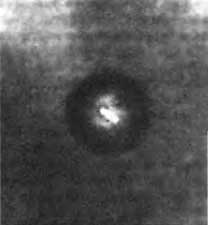

Иллюстрация к книге — Биологическая война. Введение в эпидемиологию искусственных эпидемических процессов и биологических поражений [i_045.jpg]

Рис. 1.45. Смерть в аэрозоле. На фотографии показана чумная палочка в частичке аэрозоля. Предметное стекло было предварительно окрашено основным фуксином, после чего сотрудники Форт-Детрика дали возможность частицам аэрозоля чумы осесть на стекло и исследовали их с помощью фазово-контрастного микроскопа. Длина Y. pestis 1–3 мкм. По R. J. Goodlow и F. A. Leonard (1961)